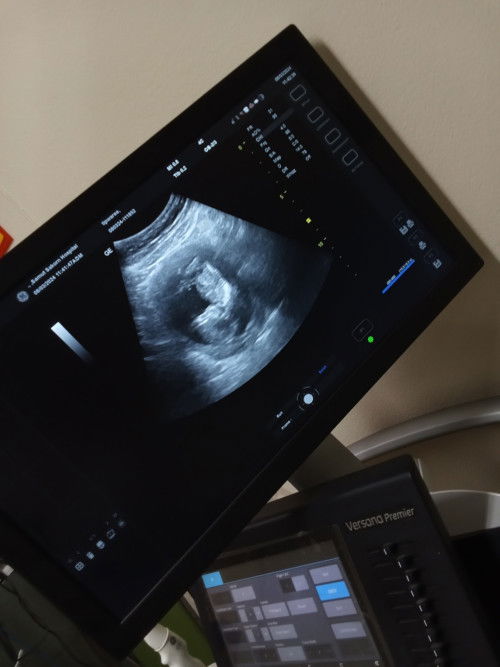

แม่มีเชื้อ Hiv ค่ะคุณหมอแจ้งว่าให้นมน้องใม่ใด้ กรณีนี้ต้องซื้อนมทานอย่างเดียวเลยใช่มั้ยคะกลัวประโยชน์จะไม่ถึง ค่าใช้จ่ายค่อนข้างสูงด้วยใช่มั้ยคะถ้าให้ใม่ใด้ตั้งแต่แรกคลอดเลย มีแบบเเม่นมแบบน้องหมาน้องแมวมั้ยคะแบบว่าแม่ๆบ้านอื่นที่น้ำนมเยอะๆแล้วเหลือทิ้ง อยากทราบข้อมูลค่ะกังวลว่าสารอาหารแล้วประโยชน์จะน้อย😢#ขอบคุณล่วงหน้าสำหรับความคิดเห็นค่ะ #ท้องแรกคะ #ขอคำแนะนำกับแม่ๆด้วยนะคะ #ขอบคุณคำตอบค่ะ